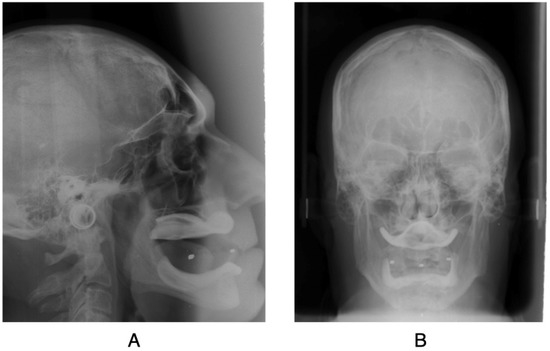

- Zygomatic plane (ZA-ZA): represents a frontal Frankfort plane.

- Frontal occlusal plane (B6L to B6R): a bisection of the molar occlusion connection represents a fronto-occlusal plane.